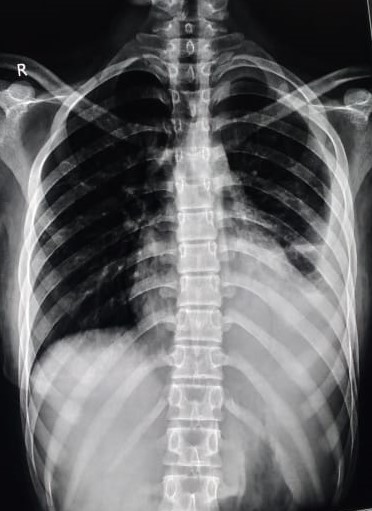

| 128 | IGGMC, Nagpur, Nagpur | P2 | 29-4344 | Surendra Chaurassiya | Consent taken on Paper | 71 Yrs. |

Provisional Diag : Dyspnea

Final Diag : ILD (Interstitial Lung Disease) |

Non-TB Case (Confirmed) | Bilateral Mid Zone & Lower Zone Reticular shadows Present & Sparium Bilateral Upper zone | Abnormality visible on x-ray |